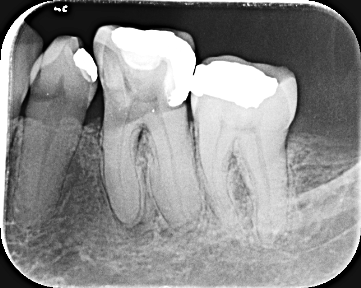

periapical digital

Radiografias Intraorales Y Extraorales